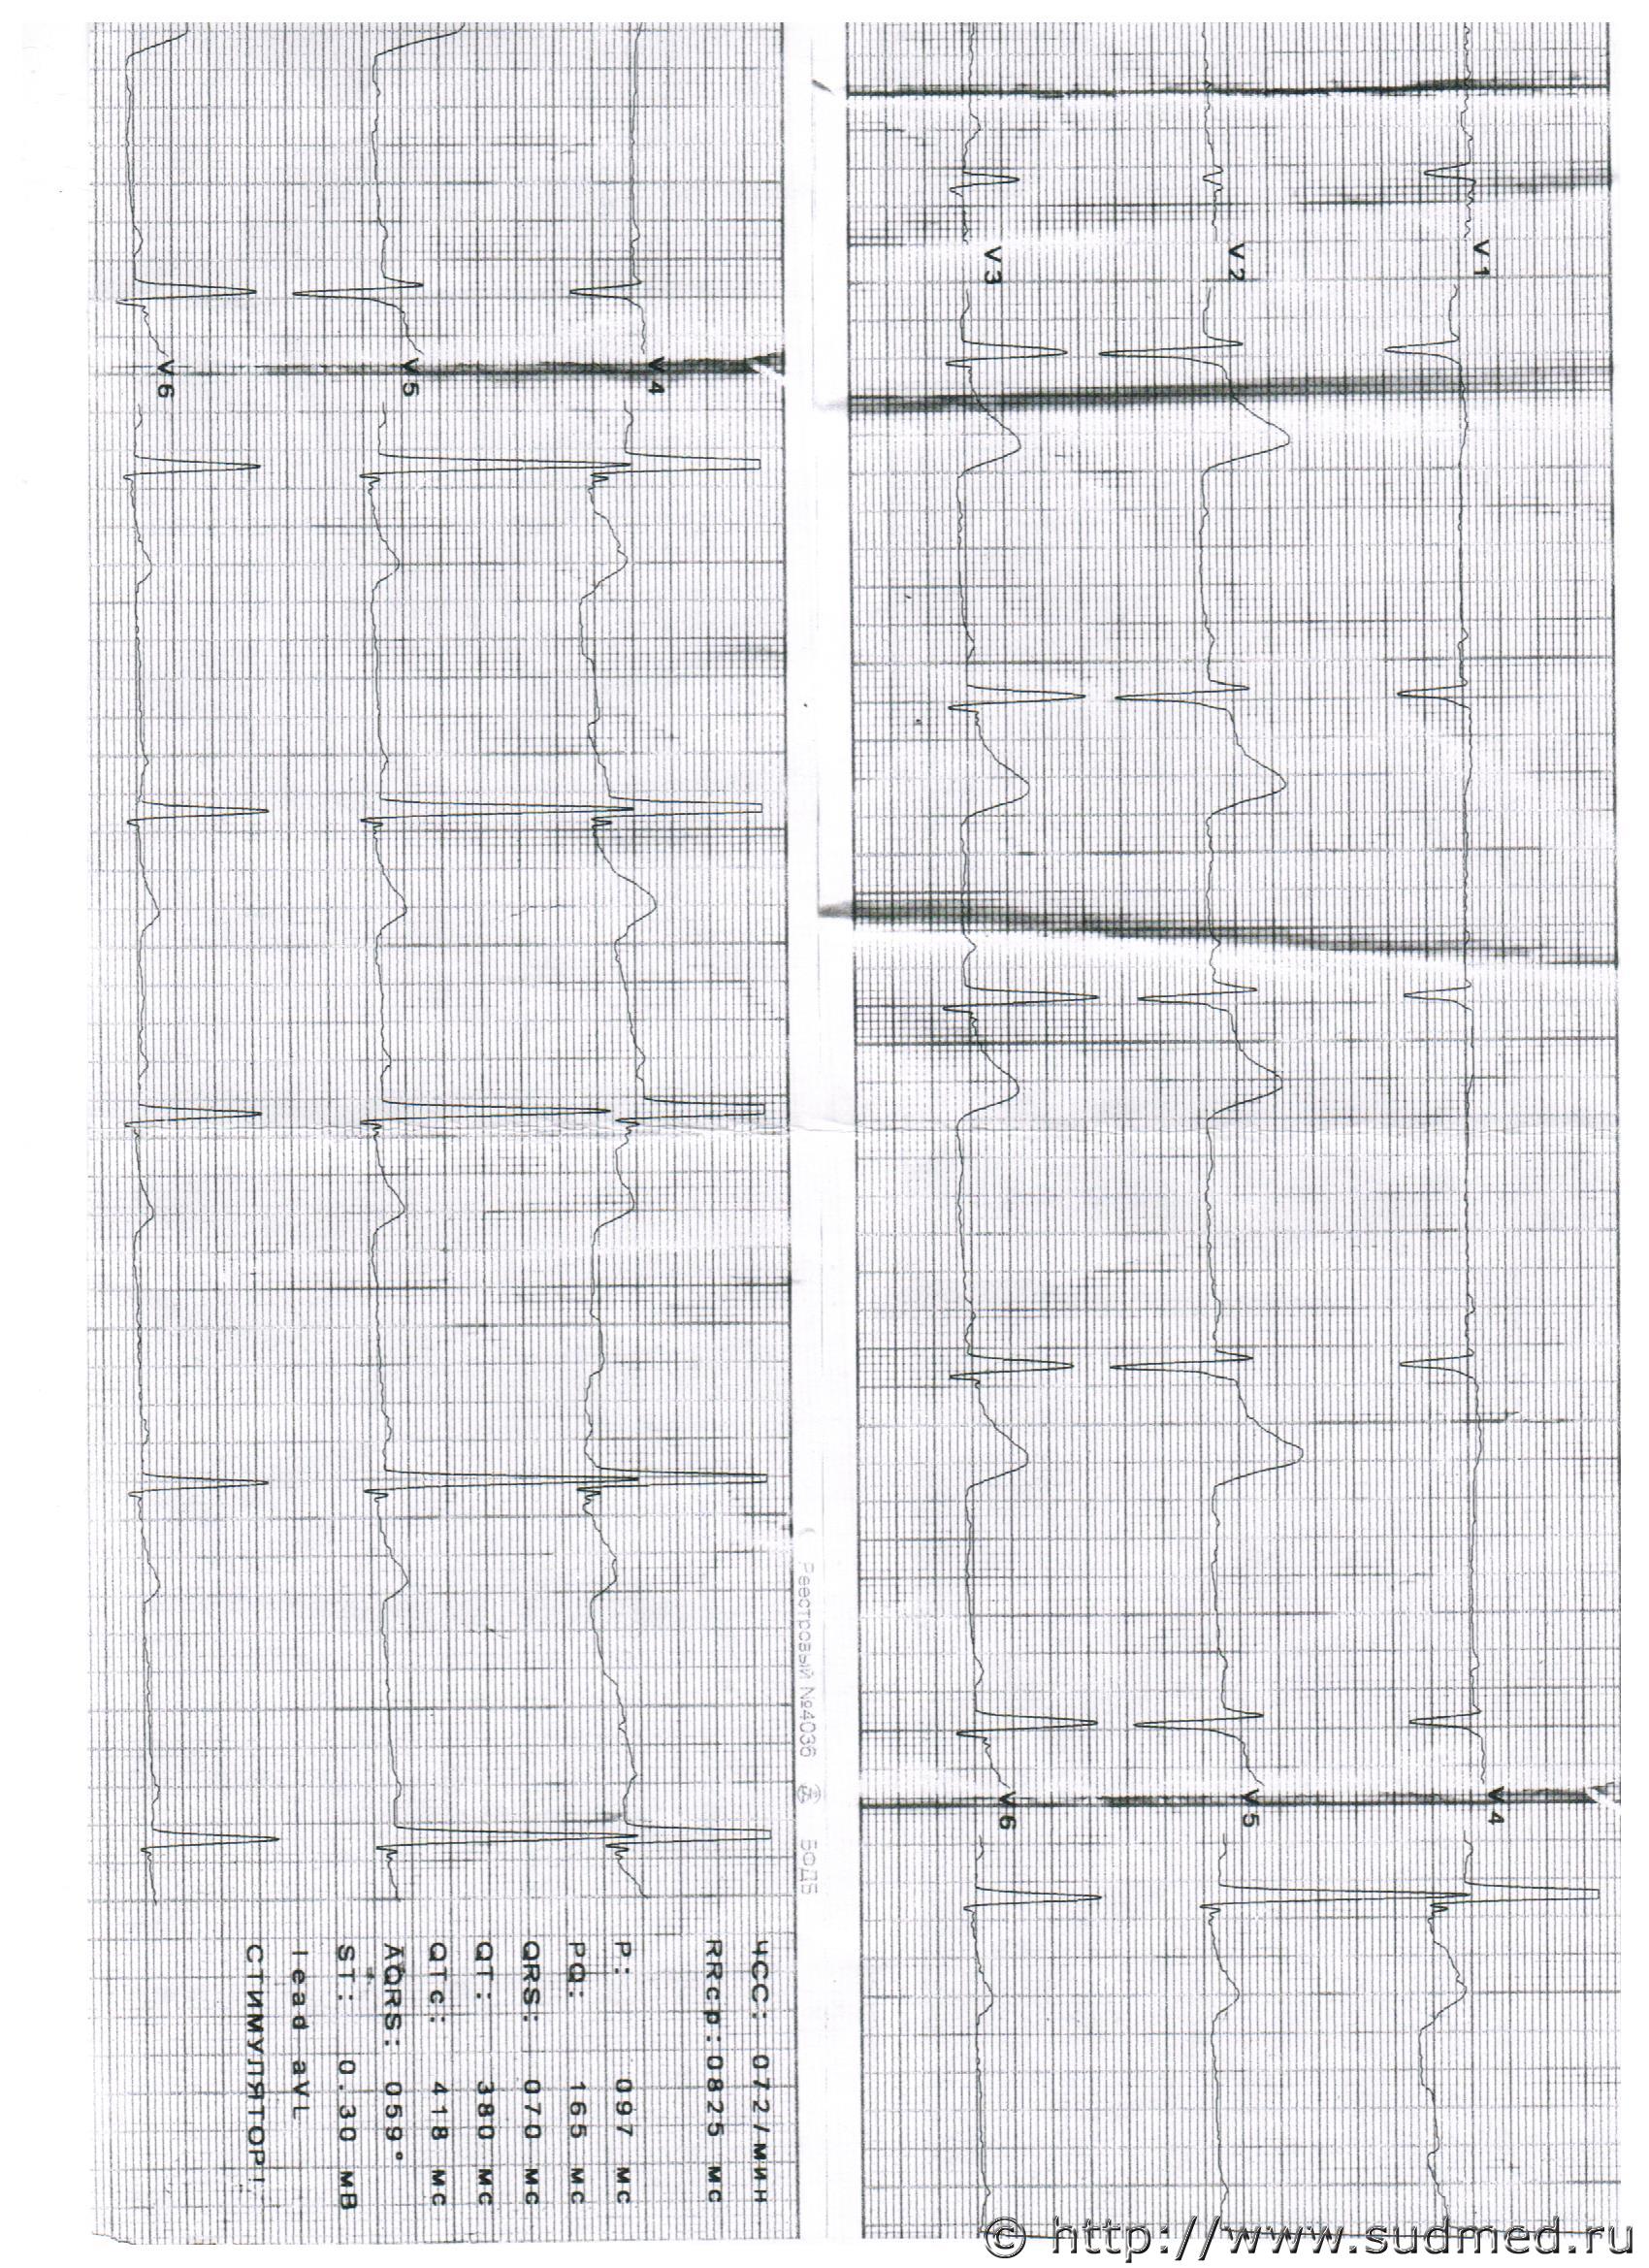

На последнем судебном заседании притащили пленки ЭКГ, которые до этого якобы были утеряны или утилизированы. Даже не знаю, как к ним отнестись. ЭКГ не выполнялось в-принципе.Описание в карте СМП не совпадает с данными пленки. Однако к материалам дела их приобщили, боюсь, что их будут рассматривать в рамках экспертизы.

Вами представленном ЭКГ данных за ОКС не наблюдается.